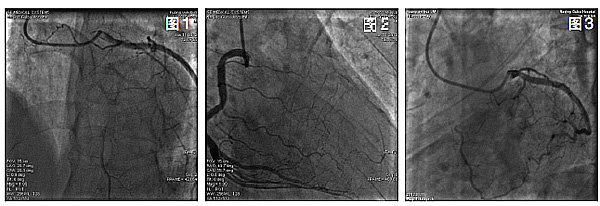

冠状动脉造影检查结果提示,左主干(LM)正常,LAD自开口处完全闭塞,远段可经回旋支(LCX)显影,LCX开口处存在局限性斑块,狭窄约30%,远段经钝缘支(OM)于心尖部与LAD远段形成2级侧支循环,右冠脉(RCA)未见明显狭窄,远段经后降支(PDA)及间隔支向LAD建立2级侧支循环(图1、2、3)。

本例患者表现为典型的劳力型心绞痛,接受冠脉造影检查,结果提示LAD呈慢性完全闭塞(CTO)病变,自LAD开口完全闭塞,无法判断LAD开口,这是对本例患者进行治疗的最大障碍。